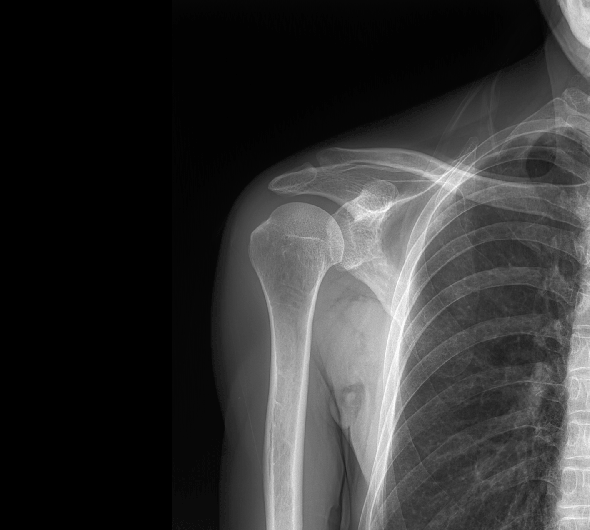

临床图像

原厂优质影像链,搭载直接生长式碘化铯非晶硅平板,带来更加清晰锐利的图像效果。